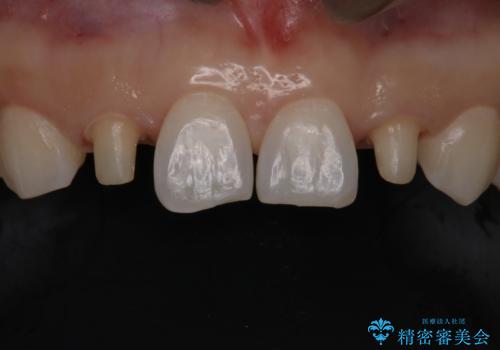

歯の形気になる!! セラミック治療 前歯( エクセレント)

- 歯の形が気になるということで以前入っていたプラスチックのものから、セラミックでの治療を希望されたので行いました。

以前使用していた被せ物を除去して、仮歯に置き換えます。

その後、歯の最終的な形を作って型取りを行います。